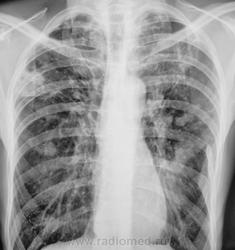

Пневмосклероз не уточненной этиологии.От туберкулезной/задействованы верхушки,уменьшена в/д справа/,до профессиональной/переломы ребер/.А вот по образованию в/д справа надо уточняться,от периферического cr до любого другого процесса.Больной сам многое расскажет.

На 99% туберкулез, с выраженными склеротическими изменениями в легких, пусть и не нашли дырки. О 100% диагнозе фтизиатры нам расскажут. Если палки есть- это одно, если нет - все равно он... Диссеминация имеет место быть. Для периферического - слишком четко все справа, хотя...

Фтизиатры признали своим, и палки есть, есть неоднократно.

По мне, справа субплеврально - периферический с прорастанием плевры. Одно другому не мешает.

картина напоминает периферический рак.  Как-то обсуждался один случай, в котором была похожая ситуация. В конце обсуждения был сделан вывод, что туберкулёз и онкология иногда идут вместе.

А периферический-то дренировался и спался... Ну и гут)))

Конечно "гут", получает массивную специфическую терапию.

Динамика есть,положительная.Ушел воспалительный процесс,остался склеротический.И,наверно,МБТ перестал сеять.Вопрос в другом,что являлось субстрактом "образования".Инфильтрация?,осумкованный междолевой плеврит?

По-моему,полость с фиброзными стенками действительно есть,но ее локализация-между латеральными стрелками(нижним полюсом прилегает к нижней стрелке)Наличие других полостей вызывает сомнение.Это скиалогия.Ничего не утверждаю,т.к.доказывать нужно оптим.тмг-ми или КТ.С уважением.

В данном случае диагноз доказан клинически,лабораторно и рентгенологически.Спасибо за интересный случай.